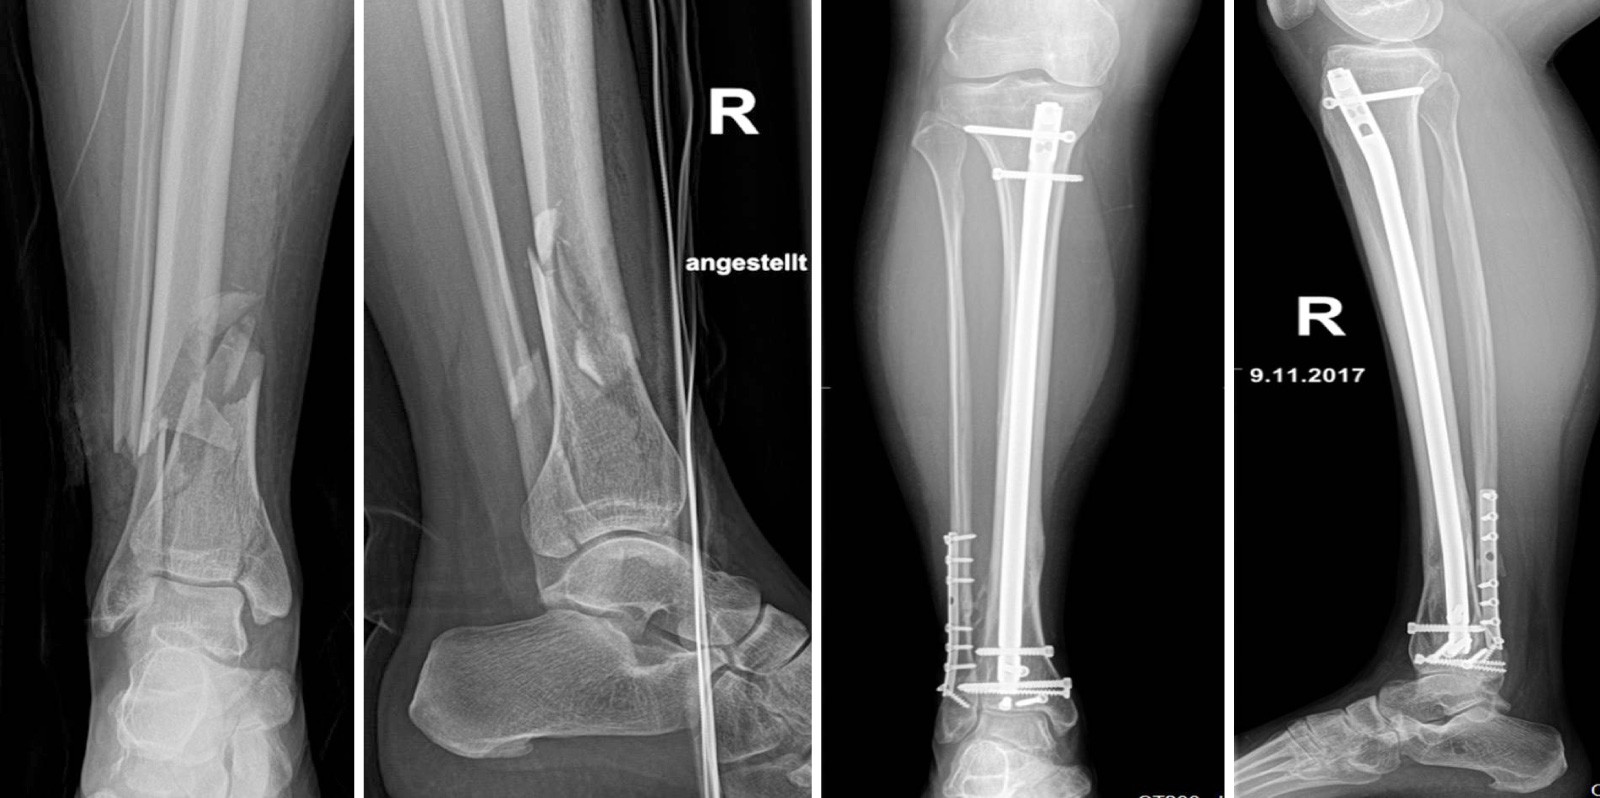

Die operative Behandlung dieser Unfallfolgen erfolgt am Klinikum Saarbrücken in enger Zusammenarbeit mit der Klinik für Anästhesiologie und Intensivmedizin. Erfahrenes und gut ausgebildetes OP-Pflegepersonal und die moderne Ausstattung der Operationssäle erlauben uns die bestmögliche Therapieplanung und -durchführung. Hierzu stehen Verfahren der Notfallversorgung, z. B. mittels Fixateur, externe moderne Osteosynthese-Verfahren, z. B. mittels Plattenosteosynthese oder Nagelosteosynthese sowie minimalinvasive Methoden zur Verfügung.

Alle unfallchirurgischen Verfahren der Notfallversorgung stehen zur Verfügung - z. B. mittels Fixateur externe, als auch moderne definitive Osteosynthese-Verfahren mittels Plattenosteosynthese oder Nagelosteosynthese sowie minimalinvasive Methoden.